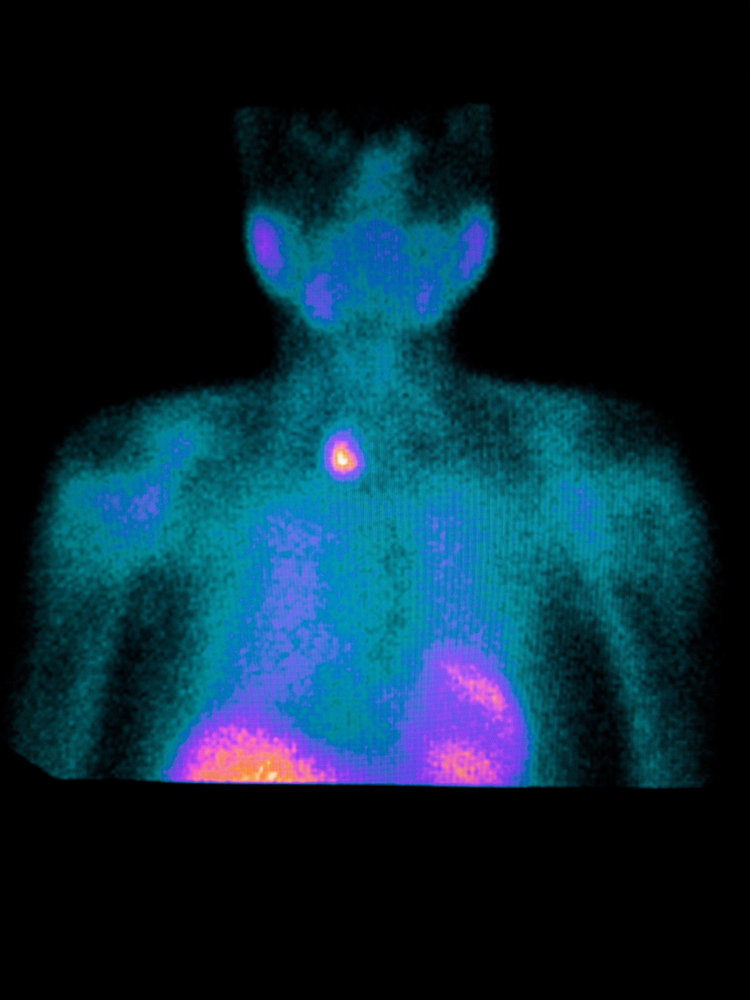

2. Parathyroid Scans Cannot Be Used to Diagnose or Exclude pHPT

Mrs. S is a 77-year-old woman from Canada who presented with “brain fog” and was found to have a serum calcium level of 10.9 mg/dL. Subsequent testing revealed a high PTH level in the context of consistently high blood calcium, high urine calcium excretion, and bone loss. She underwent a sestamibi parathyroid scan, a CT parathyroid scan, and an ultrasound parathyroid scan. None of these parathyroid scans were able to locate a parathyroid adenoma. She was told that she did not have pHPT. The diagnosis of pHPT was made several years later, only after she developed kidney stones.

If you feel a breast lump in the shower, a scan can be used to determine if a breast tumor is present. Similarly, if you cough up blood, a scan can be used to determined if a lung tumor is present. Under both circumstances, if the appropriate scans are negative, you can rest assured that you do not have a tumor.

However, when pHPT is suspected, a negative parathyroid scan cannot be used to exclude a parathyroid tumor. This is because parathyroid scans lack sensitivity. In other words, it is common for parathyroid tumors to be undetectable on parathyroid scans.

Furthermore, a positive parathyroid scan cannot be used to make the diagnosis of pHPT. This is because the specificity of parathyroid scans is not great. In other words, when a parathyroid scan shows a candidate tumor, sometimes this is a fake out (e.g., thyroid nodule or lymph node).

Overall, when someone has high calcium and PTH levels, the diagnosis of pHPT is clear, and parathyroid scans do not add diagnostic value. Furthermore, parathyroid scans should not be used to determine who should be referred to a surgeon.